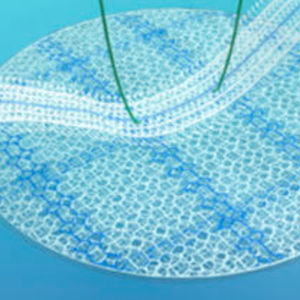

Doppelseitige Parietalprothese mitExpansionsballon (je nach Referenz). Gewebeunterstützung und Stärkung von Nabel- oder Narbenhernien. Intraperitoneale Implantation. Technische Daten Zusammensetzung Eine Seite aus monofilament ...